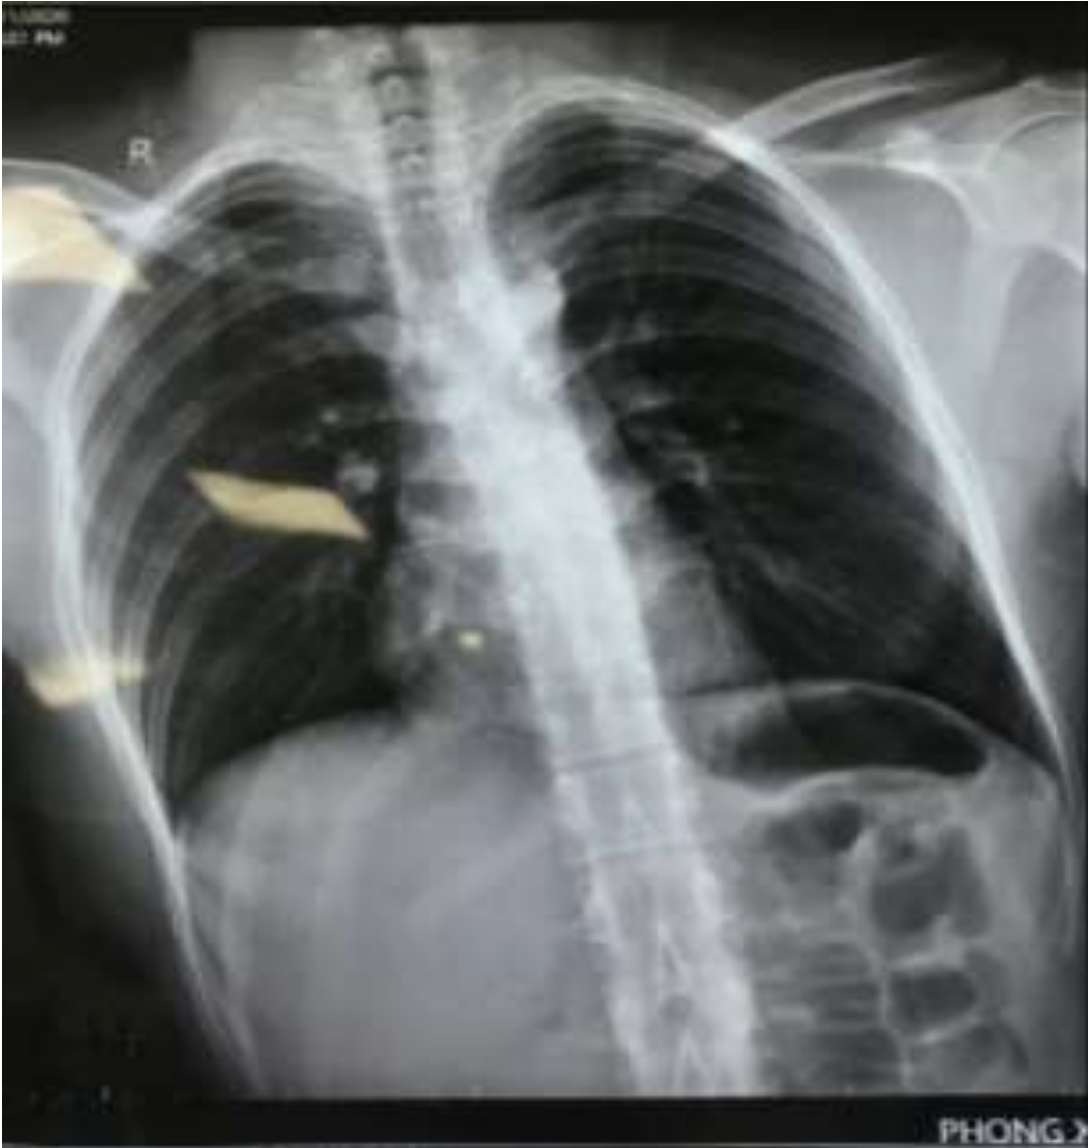

Hình ảnh X-quang ngực thẳng: Mờ lan tỏa 2 phế trường.

Kết quả điều trị, bệnh nhân rút ống nội khí quản sau 3 ngày, hình ảnh tổn thương trên X-quang và tình trạng hô hấp hồi phục gần như hoàn toàn.